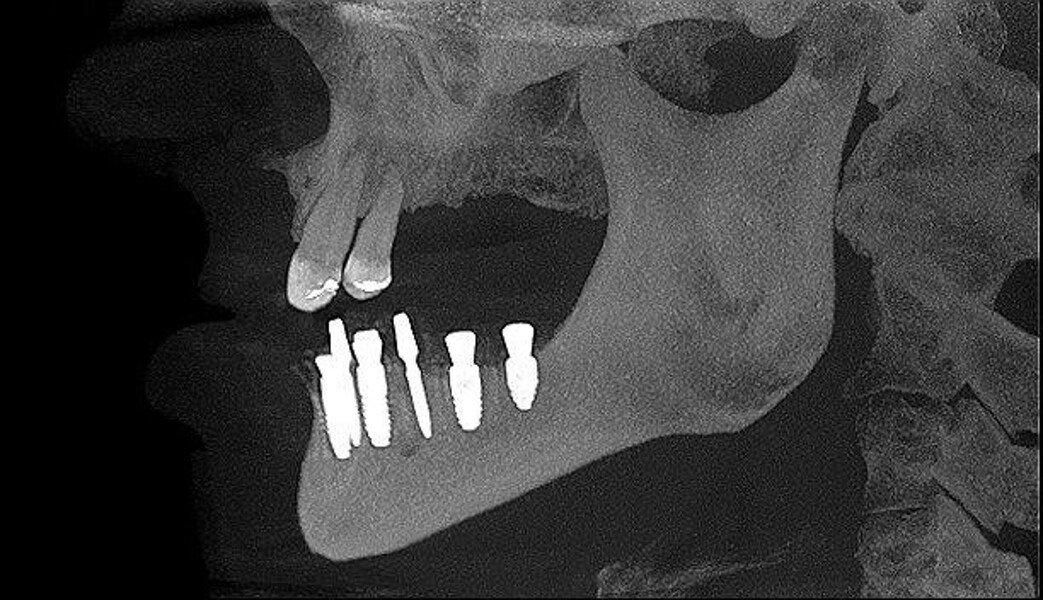

Implantacja z wykorzystaniem szablonu nawigacyjnego 3D